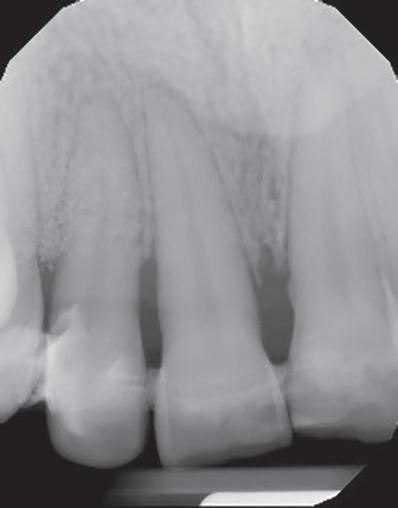

Este caso reporta los detalles de un trata miento periodontal regenerativo de los dientes 11 y 12 (sistema FDI) con movili dad severa y absceso periodontal. La pa ciente era una mujer de 27 años de edad

sin antecedentes contributivos ni aler gias conocidas, y que no estaba tomando medicamentos.

Cuando las cosas no se desarro‑ llan como estaba previsto

La paciente había comenzado un trata miento ortodóncico con un alineador transparente 6 meses antes de acudir a mi consulta. El objetivo del tratamiento orto dóntico era corregir una maloclusión cla se II de Angle con una moderada separa ción de los incisivos superiores, resalte (overjet) aumentado y proclinación de los incisivos superiores. Después de 6 meses de tratamiento, con cambios semanales de los alineadores creados por ordenador, la paciente desarrolló un absceso alrede dor del diente 12 y fue derivada a un endo doncista par drenar la lesión. Los dientes 11 y 12 se diagnosticaron como insalvables,

con profundidades de sondaje de 15 mm localizadas y movilidad de clase III. La tomografía computarizada de haz cónico (CBCT) y la radiografía periapical mostra ban pérdida de las paredes vestibular y palatina. No obstante, los dos dientes te nían un buen aporte sanguíneo, como se constató en la prueba de vitalidad pulpar. La paciente quería una segunda opinión y fue derivada a nuestra consulta.

Tratamientos periodontales y procedimientos regenerativos

El exhaustivo examen periodontal con firmó las profundidades de sondaje y la movilidad de clase III. Le explicamos los riesgos de la terapia y el pronóstico poco favorable de ambos dientes, y la paciente firmó un consentimiento informado.

Los dientes anteriores (n.º 13 23) se feru lizaron con una férula periodontal Rib bond, y la oclusión se ajustó a un contac to ligero. Se elevó un colgajo de espesor total, y el defecto se descontaminó con una combinación de láser de CO2 de 9,3 micras y EDTA al 24 %. Después de la descontaminación confirmamos un de fecto de una pared con una bolsa perio dontal intraósea de 7 mm. Injertamos el defecto con Geistlich Bio‑Oss® Collagen, que tiene una excelente capacidad para actuar como andamiaje y resulta muy útil en esta indicación.1 Después cubrimos el injerto óseo con L PRF™ para una mejor respuesta angiogénica de los tejidos.

G Radiografía periapical a los 12 meses del seguimiento. | H Hueso nuevo alrededor de los dientes 11 y 12 en la reentrada.| I Resultado final. cumplimiento del paciente, es posible re parar dientes con un pronóstico de poco favorable a insalvable. 2 4

Dientes funcionales y estéticos después de salvarlos

La paciente fue sometida a un seguimien to de 12 meses, donde se puso especial atención a la regularidad de las visitas y a la higiene oral. Al año del seguimiento y en la reentrada para mejorar el perfil del teji do blando, confirmamos que el defecto se había rellenado por completo con hueso nuevo con una adaptación estrecha a los

dientes 11 y 12. La radiografía periapical tomada en el momento confirmó las ob servaciones clínicas. Este caso destaca la importancia de realizar los diagnósticos actuales en base a los biomateriales

rados que tenemos hoy en día.

Con un uso apropiado de los biomateria les, unos protocolos de descontaminación optimizados, la técnica quirúrgica y el

| A Antes del tratamiento ortodóncico. | B CBCT periapical antes del tratamiento periodontal. | C Dientes (13 y 23) ferulizados. | D Bolsa intraósea de 7 mm después de abrir el colgajo. | E Geistlich Bio-Oss® Collagen rellenando el defecto. | F Membrana L-PRF™ bioactiva cubriendo el injerto óseo. |